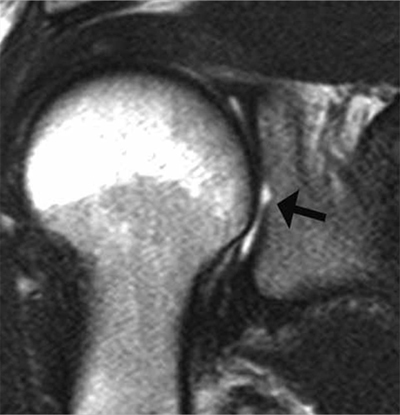

Figure 6

Bare area of the glenoid on MRI. Coronal oblique PD-weighted MR image displays a defect in the cartilage filling up with a moderate amount of joint fluid (arrow) without any thickening of the subchondral bone. As for the tubercle of Assaki, the bare area of the glenoid may be mistaken for a cartilage ulceration.